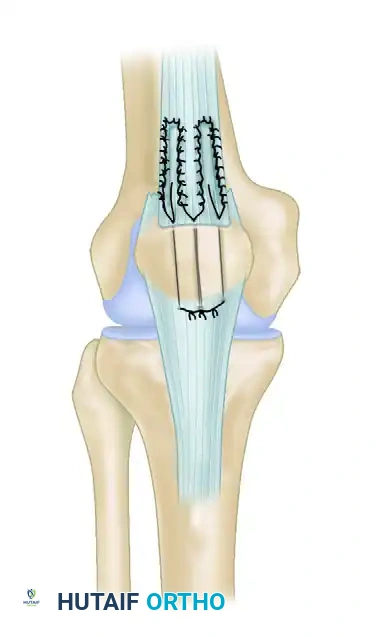

4. Graft Routing and Fixation

- Create a transverse osseous tunnel through the mid-portion of the patella using a 4.5-mm or 5.0-mm cannulated drill over a guide pin. Ensure the tunnel is strictly in the coronal plane to avoid violating the articular surface.

- Create a second transverse osseous tunnel through the tibial tuberosity.

- Pass the unified hamstring graft through the transverse hole in the patella and then route it distally through the transverse hole in the tibial tuberosity in a figure-of-eight fashion. This configuration provides exceptional biomechanical stability and acts as an internal splint for the healing extensor mechanism.

- Tension the graft with the knee in full extension.

- Use running interlocking sutures, as described by Krackow, Thomas, and Jones, to suture the hamstring tendon graft to itself at the crossover points of the figure-of-eight.

- Tack the hamstring tendons securely to the underlying native patellar tendon and quadriceps tendon using multiple interrupted nonabsorbable sutures.

- Thoroughly irrigate the wound, achieve hemostasis, and close the retinaculum, subcutaneous tissue, and skin in a layered fashion.